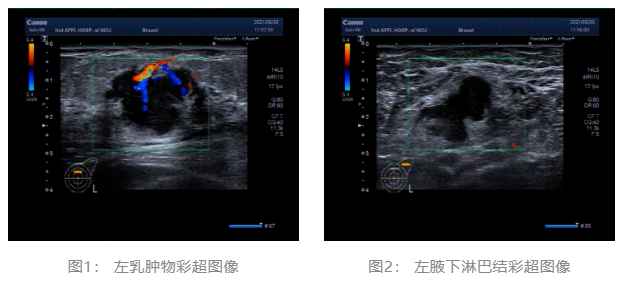

2021.06.30 乳腺彩超:左侧乳腺低回声团块,BI-RADS-US 4c类。左侧腋窝肿大淋巴结。(图1、2)

2021.06.30 胸部CT平扫:1.左乳占位伴左侧腋窝区肿大淋巴结 2.双肺未见明显异常(图7、8)